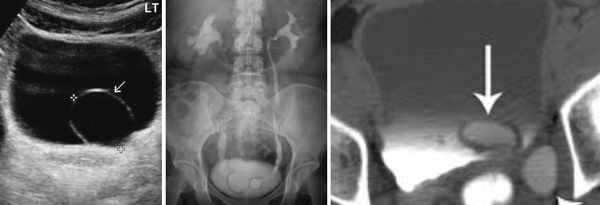

(Слева) МЦУГ в прямой косой проекции: у младенца мужского пола с анамнезом инфекции мочевыделительных путей определяется округлый дефект наполнения мочевого пузыря с гладкой поверхностью. Эти признаки характерны для уретероцеле.

(Справа) После дальнейшего растяжения мочевого пузыря уретероцеле вывернулось наружу из просвета мочевого пузыря. Выворот уретероцеле можно ошибочно принять за дивертикул мочевого пузыря.

(Слева) КТ мочевого пузыря без контрастирования, аксиальный срез: два плотных кальцинированных конкремента в области левого МПС.

(Справа) Аксиальная проекция того же среза, полученная в отсроченную урографическую фазу: конкременты находятся внутри уретероцеле. Иногда дифференциальная диагностика между врожденным уретероцеле, содержащим камни и приобретенным расширением терминального отдела мочеточника при обструкции конкрементом (так называемое «певдоуретероцеле») может представлять трудность.

(Слева) Экскреторная урография: полное удвоение левых мочеточников с эктопией уретероцеле в области шейки мочевого пузыря. Дефекты наполнения в расширенной части мочеточника представляет из себя кистозный уретерит.

(Справа) КТ с контрастированием, корональный срез: внутрипузырное уретероцеле с cony ствующим расширением мочеточника и чашечек. Гидронефроз встречается относительно редко и обычно не выражен у пациентов с внутрипузырными уретероцеле.